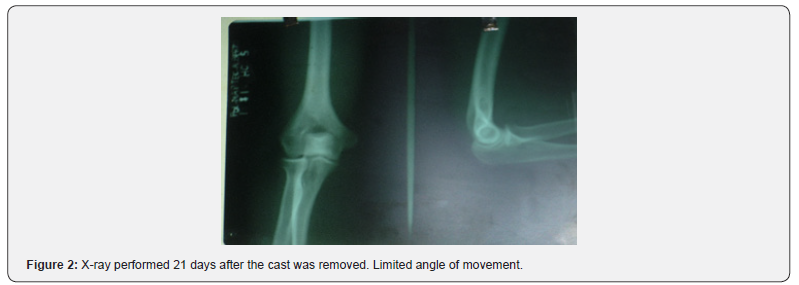

The patient was transferred to the operating room where reduction was carried out under anesthesia in the supine position. Two specialists intervened in the procedure, one of whom fixed the patient’s arm against the examination table while the second specialist performed slow continuous traction. and firm in the direction of the humerus axis by grasping the wrist, keeping the forearm slightly flexed and the wrist slightly supinated. The control X-ray was satisfactory and clinically stable. A posterior brachiopalmar splint was placed for 6 days and a circular brachio-palmar cast for 15 more days, with good recovery of function, which was evidenced in the control X-ray (Figure 2). Nerve paralysis or vascular injury was not observed. The evolution was excellent after two months of rehabilitation (Figure 3).

After reduction, posterior splint immobilization is performed for 1–3 weeks [7]. In the case presented, the reduction was carried out early and afterwards immobilization with a splint and plaster, which affects a good prognosis of evolution. After three weeks of immobilization, rehabilitation of the limb should be performed consisting of controlled flexion and extension with an orthopedic elbow for another 4 weeks. The estimated time of temporary disability is 10 to 12 weeks. [1]. Mobility in this case was recovered after 8 weeks of treatment, with good recovery of limb strength. Complications of traumatic elbow dislocation include neurovascular injury, limited range of motion, and elbow instability [2,3]. Arterial injuries are estimated to occur in approximately 5% to 13% of elbow dislocations. .[two] The incidence of re-dislocation after simple elbow dislocation is low [8]. The aforementioned case did not present neurovascular injury but did have limited mobility ranges and elbow instability; however, its evolution was rapid and satisfactory. Due to the large displacement already described in this case and the severe capsuloligamentous soft tissue injury, ulnar nerve injury was to be expected; In addition, the pressure of the olecranon in external position and maintained against the skin was also to be expected, necrosis of the same, luckily none of these unfavorable events happened. According to the trends of orthopedic or conservative treatment used internationally [1,2], the dislocation was reduced, and immobilization was maintained for 3 weeks so that these highly affected soft tissues had the time necessary for healing; a complete joint function was obtained, with full incorporation to their activities in a short time, without sequelae, after physiotherapy.